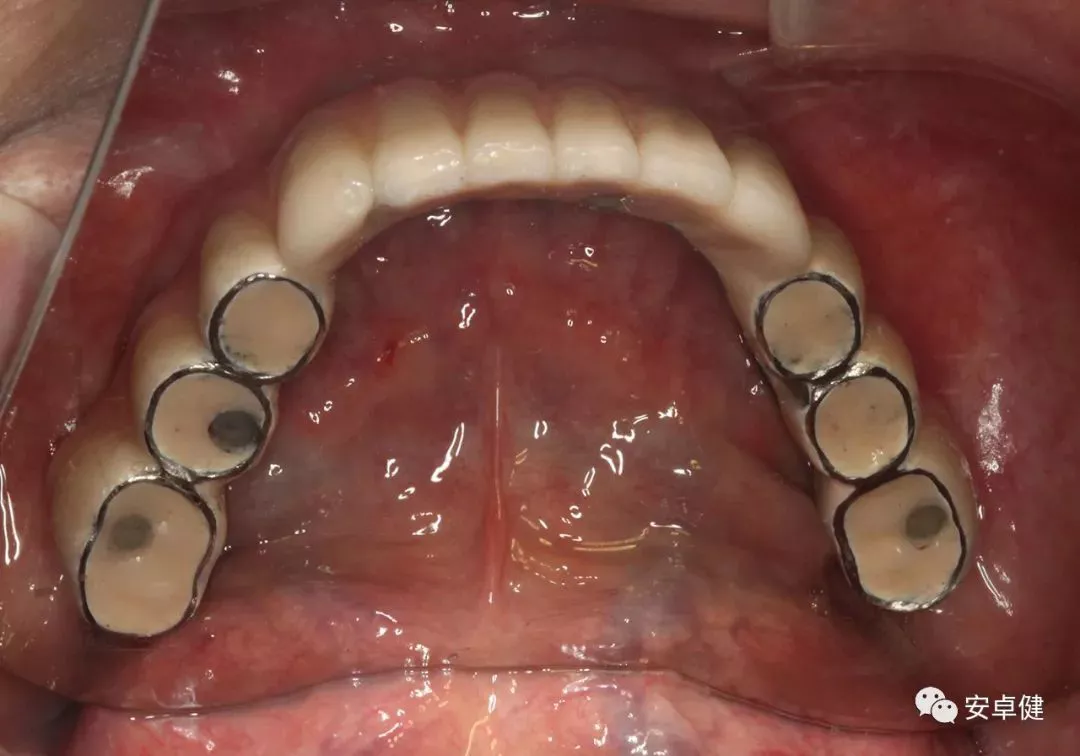

术后13个月复查拆除下颌过渡义齿合面照

戴最终修复体合面观

▷ 永久修复

• 于口内试戴原厂纯钛切削一体式桥架,并检查前牙排蜡外形及后牙咬合关系;

• 聚合瓷烤塑制作最终修复体;

• 为减少牙面磨耗,于后牙区制作360度防裂纯钛金属带;

• 试戴满意后,二级螺丝加力至15N;

• 特氟龙封闭螺丝孔,光固化复合树脂封闭上方螺丝通道,完成最终固定式种植义齿修复;

• 修复体外形能够正确恢复面下1/3高度及侧貌;

• 患者可获得较为稳定的咬合关系,并满足其咀嚼功能的需求;

• 患者42、46部位牙龈退缩,缺乏足够的角化龈,为方便后期清洁维护,选择穿龈较高的龈上肩台;

• 口内观察,修复体边缘金属基台颜色暴露,但由于其处于下颌后牙非微笑暴露区,故对临床整体美观效果的影响在患者可接受范围内。